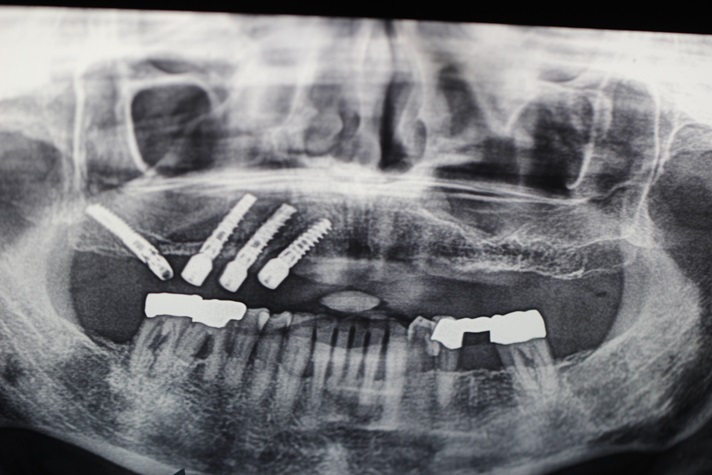

Tall and Tilted Pin Hole Immediate Loading ( TTPHIL) is a modern and most reliable technique for dental implantation. The special feature of such method is that dentist combine long and wide implants with bi-cortical support bone.

The All on 6 and All on 4 technique apply that method of implants placement.

This case report show the successful All on 6 dental implantation using Alpha Dent implants.